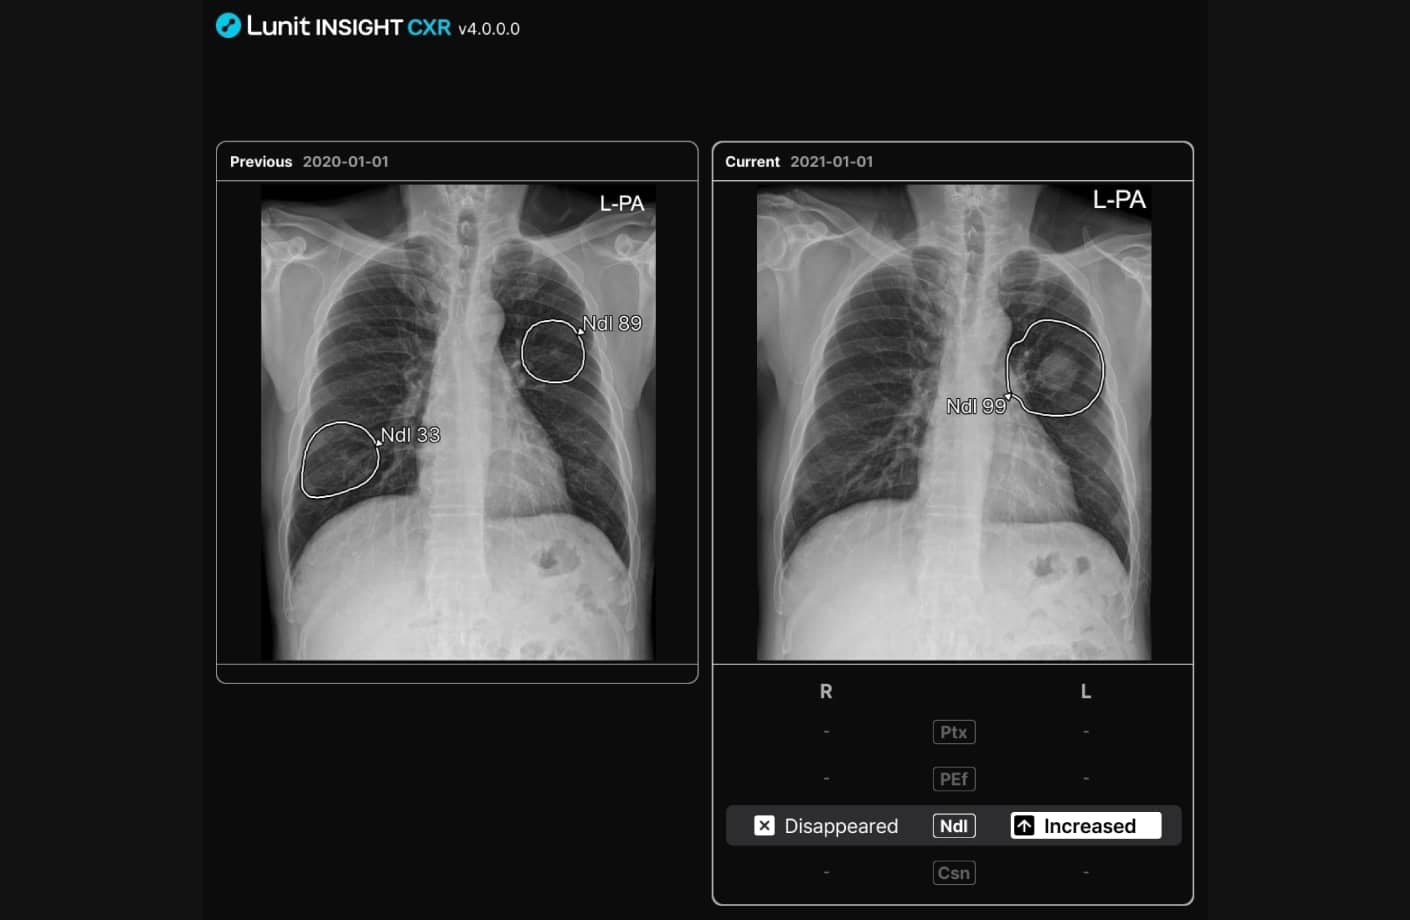

Boost precision across readers with AI that highlights 11 major thoracic abnormalities with 95-100% AUC* (and supports tuberculosis screening), compares priors, and supports earlier diagnosis.

Lunit INSIGHT CXR is a clinically validated X-ray AI solution for your entire CXR pathway. It integrates seamlessly with current workflows and assists radiologists in identifying both common and complex pathologies with greater speed and precision.

Lunit INSIGHT CXR achieves up to 100% accuracy* in detecting 11 major thoracic abnormalities—including nodules, pneumothorax, consolidation, pleural effusion, and fractures. Its performance has been independently validated on more than 250,000 chest X-rays.